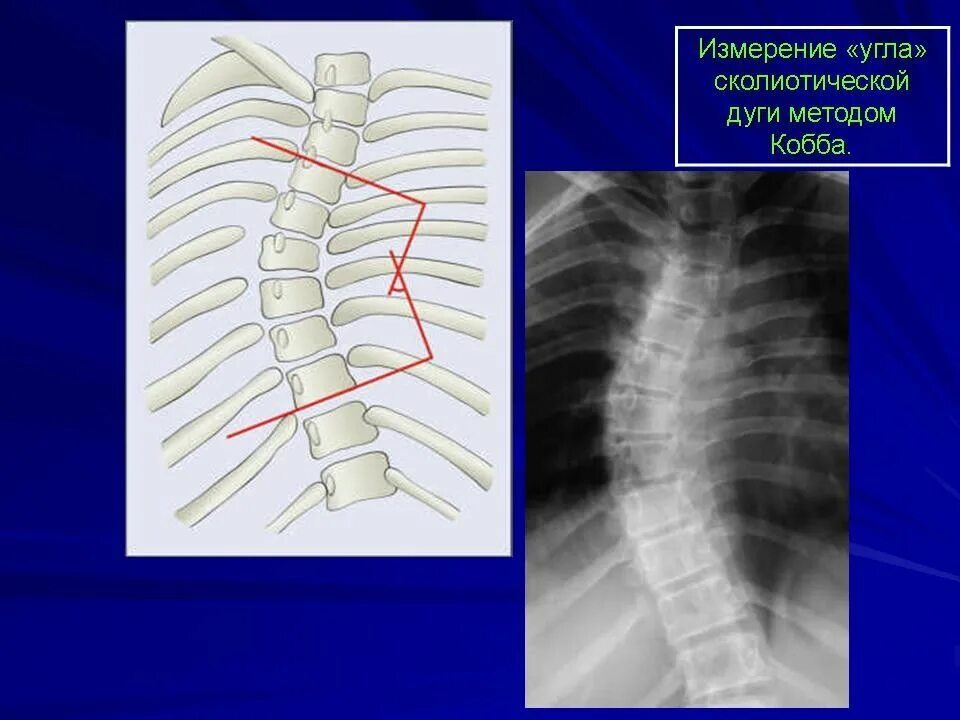

Деформация позвоночных